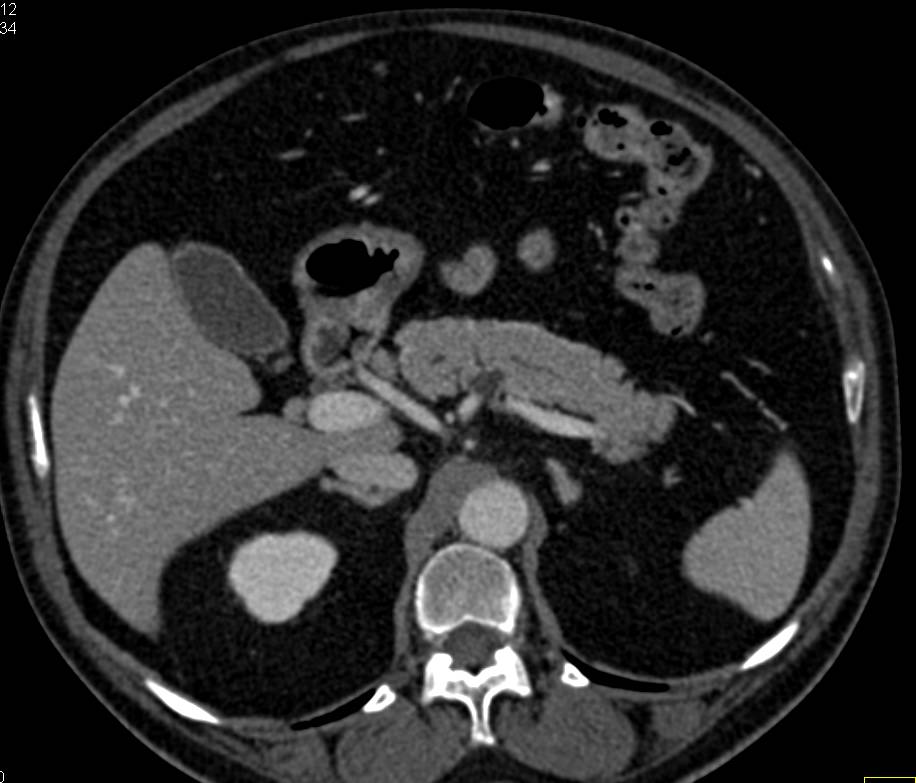

Pancreatic Cancer in Head of Pancreas and Multiple Intraductal Papillary Mucinous Neoplasms (IPMNs)